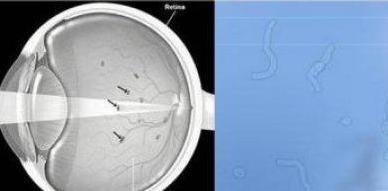

飞蚊症,听起来是不是觉得有点陌生?其实,它是一种常见的眼部疾病,主要表现为眼前有飘动的小黑影,就像蚊子飞过一样。虽然不影响视力,但那种感觉真的很不舒服,就像有一只小虫子在眼前飞来飞去,让人心烦意乱。